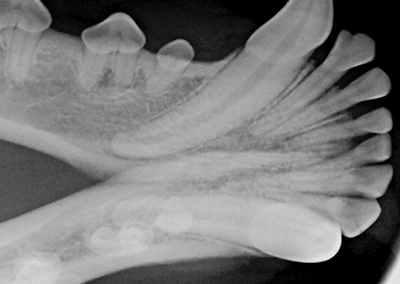

• Fogászati RTG digitális  iM3 technikával